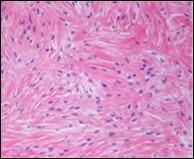

Macroscopically,the neoplasm is gradually progressive, painless, firm, tan coloured, well circumscribed, grossly infiltrative, soft tissue mass of magnitude varying from one centimetre to 18 centimetres, commonly of 6 centimetres diameter. Cut surface is fibrotic with focal myxoid areas4. On fine needle aspiration cytology, the cellular neoplasm is configured by spindle-shaped cells. Tumour cells contain scant, wispy cytoplasm, uniform, elongated nuclei and miniature, inconspicuous nucleoli. The background is prominently myxoid. Significant nuclear pleomorphism or mitotic activity is absent. However, cogent diagnosis on cytology may be challenging 4.5. On low power, the well demarcated neoplasm is composed of alternating foci of myxoid and fibrous tissue. Giant rosettes are intermingled with zones of whorled cellular aggregates recapitulating preliminary rosettes.

Bland tumour cells depict monotonous, hyperchromatic nuclei. Tumour areas can exhibit prominent curvilinear, arching or plexiform vasculature. Mitotic activity is exceptional 4, 5.

Typically, low grade fibromyxoid sarcoma is comprised of a whorled cellular pattern with intermingled fibrous and myxoid areas. Also, minimally cellular areas of collagenous tissue are denominated, composed of uniform spindle-shaped cells4, 5. Unique morphologic pattern of hyalinising spindle cell tumour configuring giant rosettes can appear in certain low grade fibromyxoid sarcomas4, 5.

The minimally to moderately cellular neoplasm is composed of bland, fusiform or spindle-shaped cells with scarce cytoplasm and angulated nuclei. Also, whorled cellular aggregates are exhibited. Focal to diffuse cellular whorls are intermingled within a dense, collagen-rich stroma. Abrupt, focal transition to myxoid areas can be discerned. Roughly 45% neoplasms depict foci of epithelioid cells. Nearly 40% tumours display enlarged, inadequately configured collagen rosettes2, 4.

The neoplasm frequently infiltrates abutting skeletal muscle. Occasionally, tumefaction denominates hyper-cellular foci, tumour necrosis, cellular or nuclear atypia and mitotic figures, features which are characteristic of intermediate to high grade sarcoma. Localized tumour reoccurrence may be hyper-cellular with enhanced mitotic activity 4, 5. On ultrastructural examination, fibroblastic differentiation is exemplified 5. Figure 1, Figure 2, Figure 3, Figure 4, Figure 5, Figure 6, Figure 7, Figure 8.

Figure 1.Low grade fibromyxoid sarcoma enunciating fibrous and myxoid zones of uniform spindle-shaped tumour cells with absence of atypia 9.